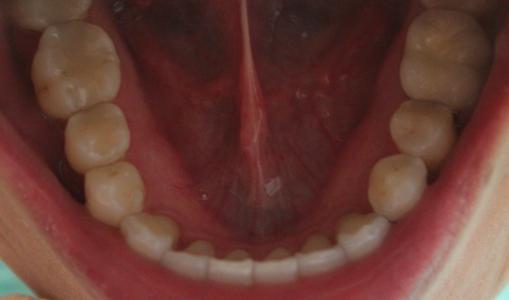

The crowding of this patient's teeth could have led to issues, including buildup of plaque and tartar, harbors harmful periodontal bacteria, risk of periodontal disease, tooth, and bone loss. After one year of Invisalign treatment, teeth have aligned properly for a healthier mouth.

a top-down view of a patients mouth before recieving an invisalign treatment | invisalign dentist vienna va a top down view of a patients lower teeth after receiving invisalign | invisalign dentist vienna va